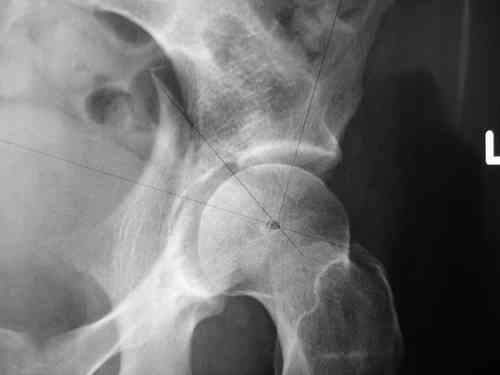

Dear group, 30 years age female MVA front seat, head trauma + post column left acetabular fracture, 2.5 weeks skeletal traction. She is now conscious but still confused without any surgical treatment for brain edema.

Latest X rays and CAT is attached. Fracture within first 1.5 cm from the weight bearing dome, although AP and Obtrator oblique good, iliac oblique view reveals some displacement. I'm not sure that nonsurgical treatment will be OK Hüseyin Demirors Baskent University Dept of Orthopedics and Travmatology Ankara TURKEY